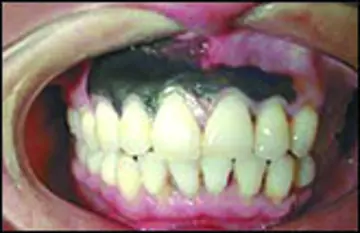

ملانـوم لثـه